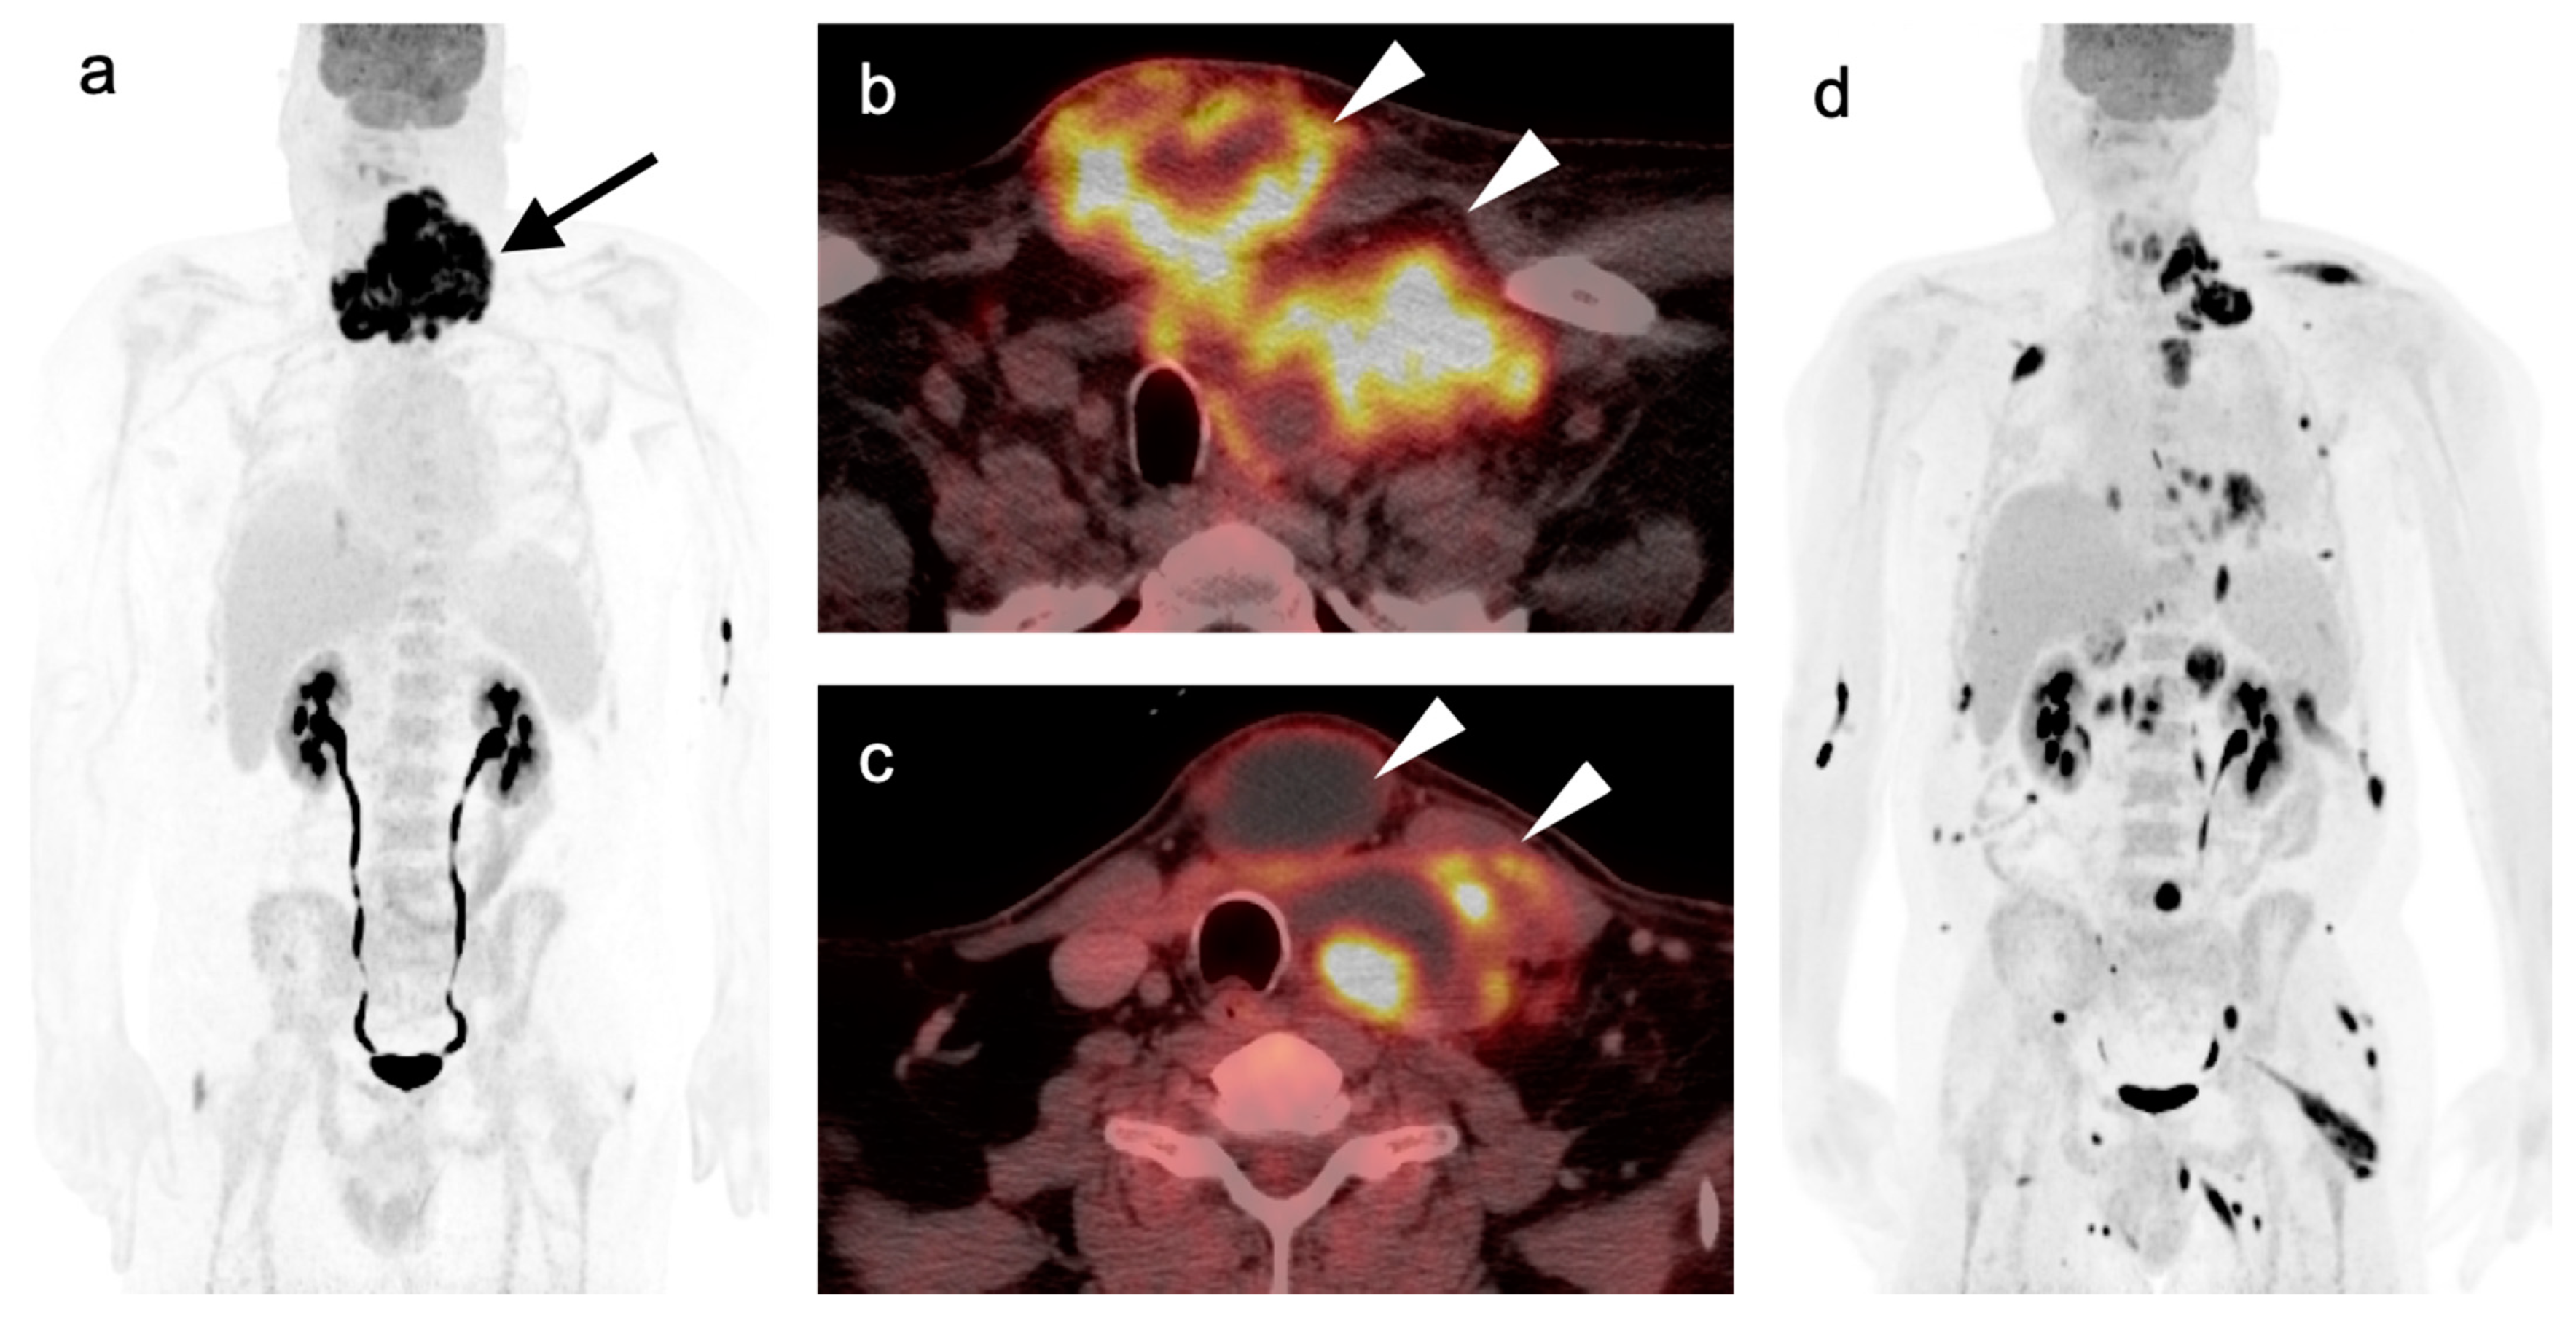

2.6. Thyroid Cancer

- Anaplastic thyroid cancer

- Medullary thyroid cancer